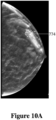

• Figure 10A shows the image of a human breast generated from a volumetric image reconstructed from a number of 2D X-Ray images produced by a DBT device, where the generated 2-D projection image was formed at a specific angle, where a micro calcification is occluded by denser breast tissue, as represented in Figure 7A .

• Figure 10B shows the generated 2-D projection image of the human breast formed from a different angle to that shown in Figure 10A , where the micro calcification is visible and not occluded by the denser breast tissue, as represented in Figure 7B .